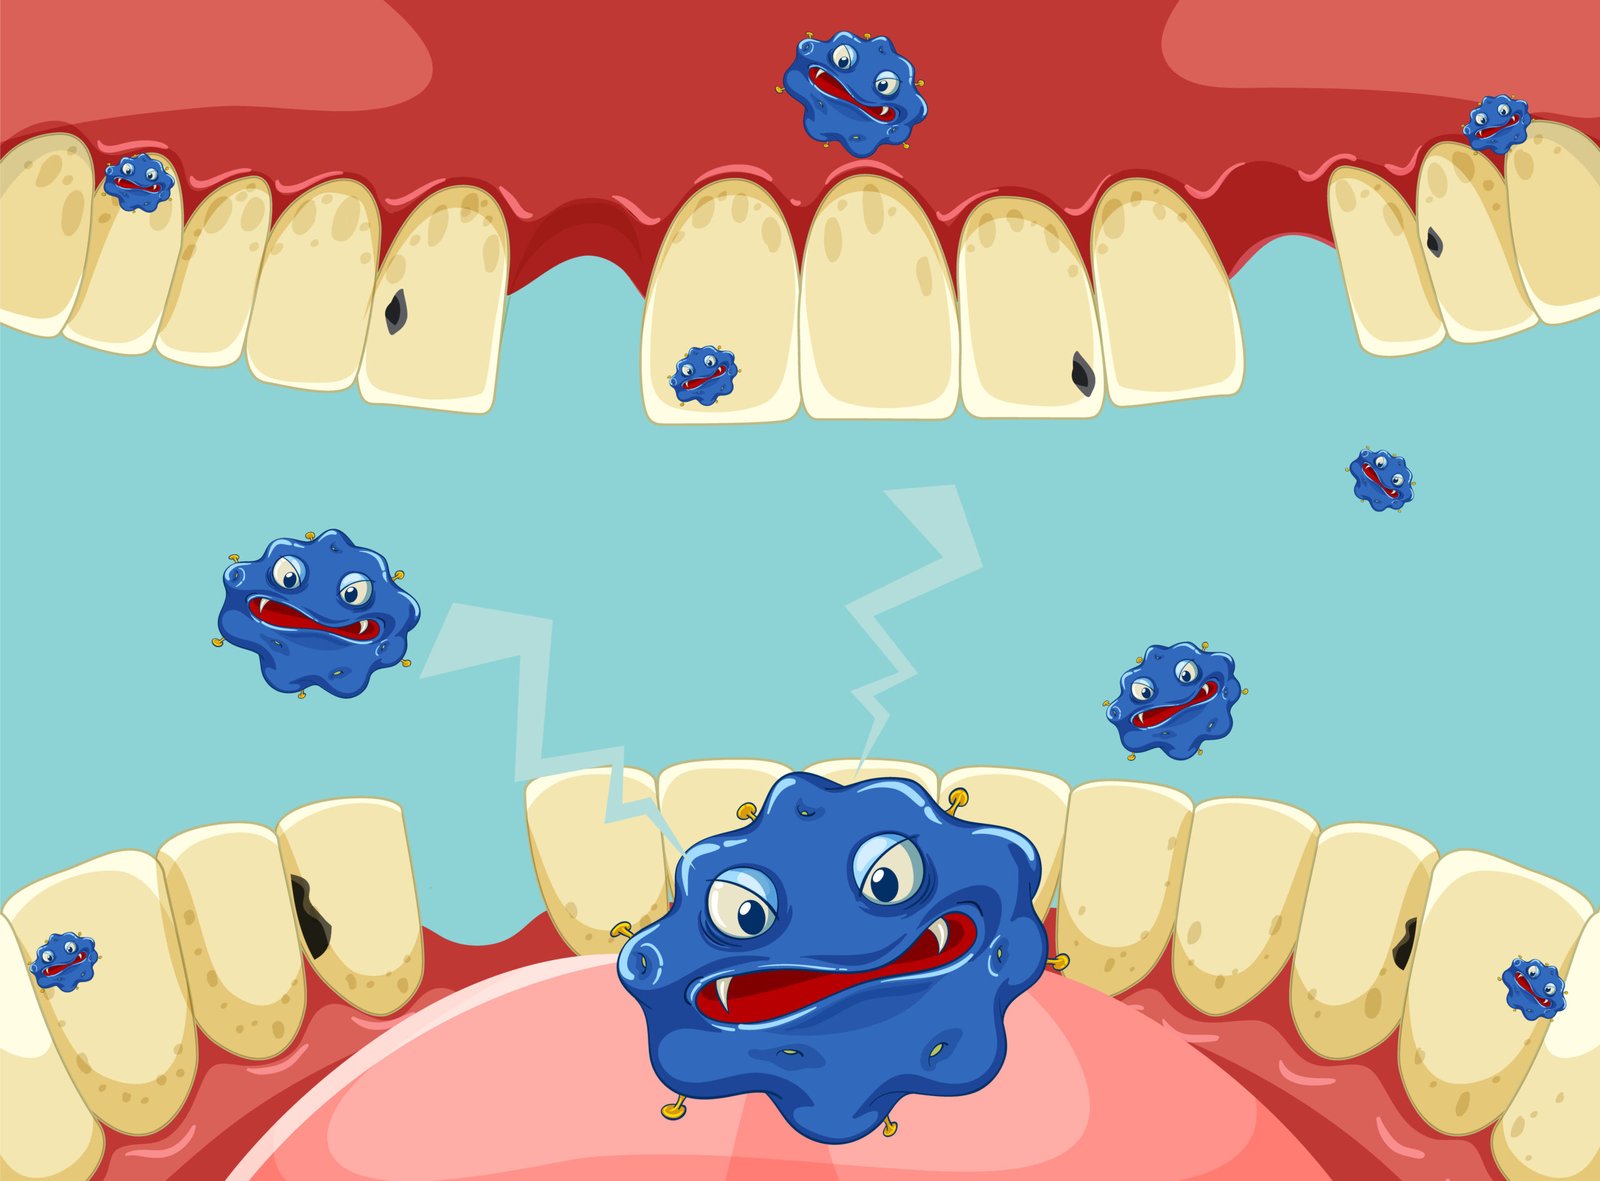

- Oral Microbiome: The ecosystem of microorganisms in the mouth plays a role in oral health. Body shifts of this balance can result in dental caries (cavities) and gum diseases like gingivitis and periodontitis.

Preventing Dental Problems

Using these pre-emptive steps, you can minimize the occurrence of cavities, gum disease (gingivitis and periodontitis), tooth erosion, and tooth infections such as a tooth abscess. Preventive dentistry not only maintains your smile, but it also prevents the long-term and expensive dental treatments later in life. Patient education and professional guidance are central in facilitating good preventive behaviors.